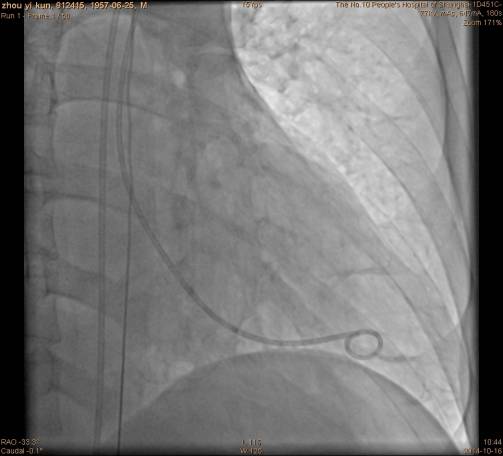

穿刺左侧股动脉,置入6F鞘管,行左心室造影;

手术过程左心室造影: